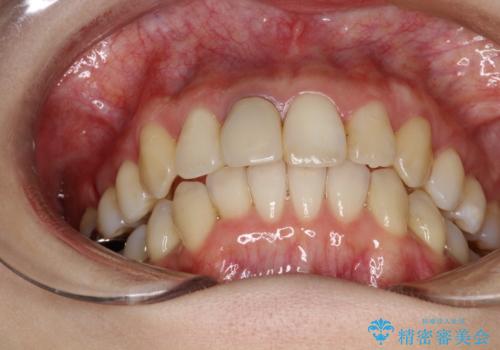

- 上下のがたつきを主訴に来院された患者様です。

上下の前歯と奥歯にがたつきがありました。

上下の奥歯を後方に移動させるのと、歯と歯の間をわずかに削ることでスペースを作り、歯を並べる計画としました。

インビザラインにて治療を行いました。

比較的がたがたの度合いが大きかったですが、しっかりとマウスピースを使用していただけたので、順調に治療を終えることができました。